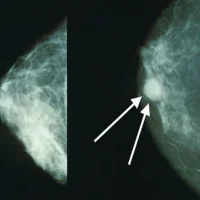

The new technology – biomarker ratio imaging microscopy, or BRIM – can identify aggressive forms of ductal carcinoma in situ (DCIS), or stage 0 breast cancer, from non-aggressive varieties, according to researchers at the University of Michigan.

Rates of DCIS have increased ever since screening mammography became common and some experts believe that DCIS can develop into invasive breast cancer, a theory that has not yet been proven. Currently, there is not a way to stratify the disease based on aggressiveness.